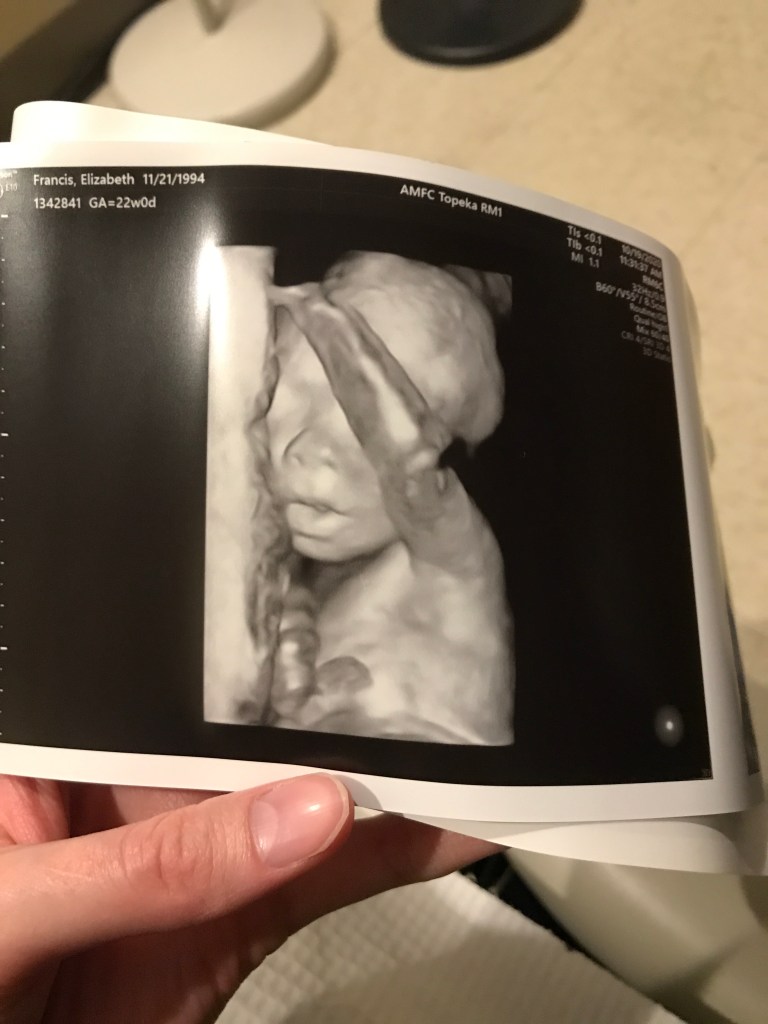

In June, we got a BIG surprise when we found out that I was pregnant again. We are due around Valentine’s Day with another boy. Ellie keeps putting orders in for a sister but Austin and I keep getting her order all wrong.